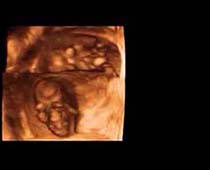

- صور لوجه الجنين في داخل الرحم

- صور جانبية لرأس الجنين

صور لأجنة ثلاثية الأبعاد بجهاز الموجات فوق صوتية | الدكتور نجيب ليوس